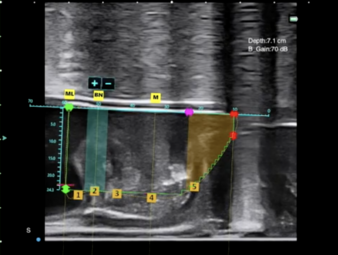

對於前列腺體積特別巨大的病人,一般較難把大部份前列腺組織有效地切除。在這種情況下,可以考慮其他的治療方案,例如前列腺水刀消融術和雙極/鈥激光前列腺剝離術。進行前列腺水刀消融手術的時候,我們會先在超聲波圖像上標記前列腺的輪廓,然後通過機械人控制的水射流技術進行消融。進行雙極/钬激光前列腺剝離術的時候,我們會先認清前列腺包膜的位置、然後把前列腺組織剝離及移除。

前列腺水刀消融手術